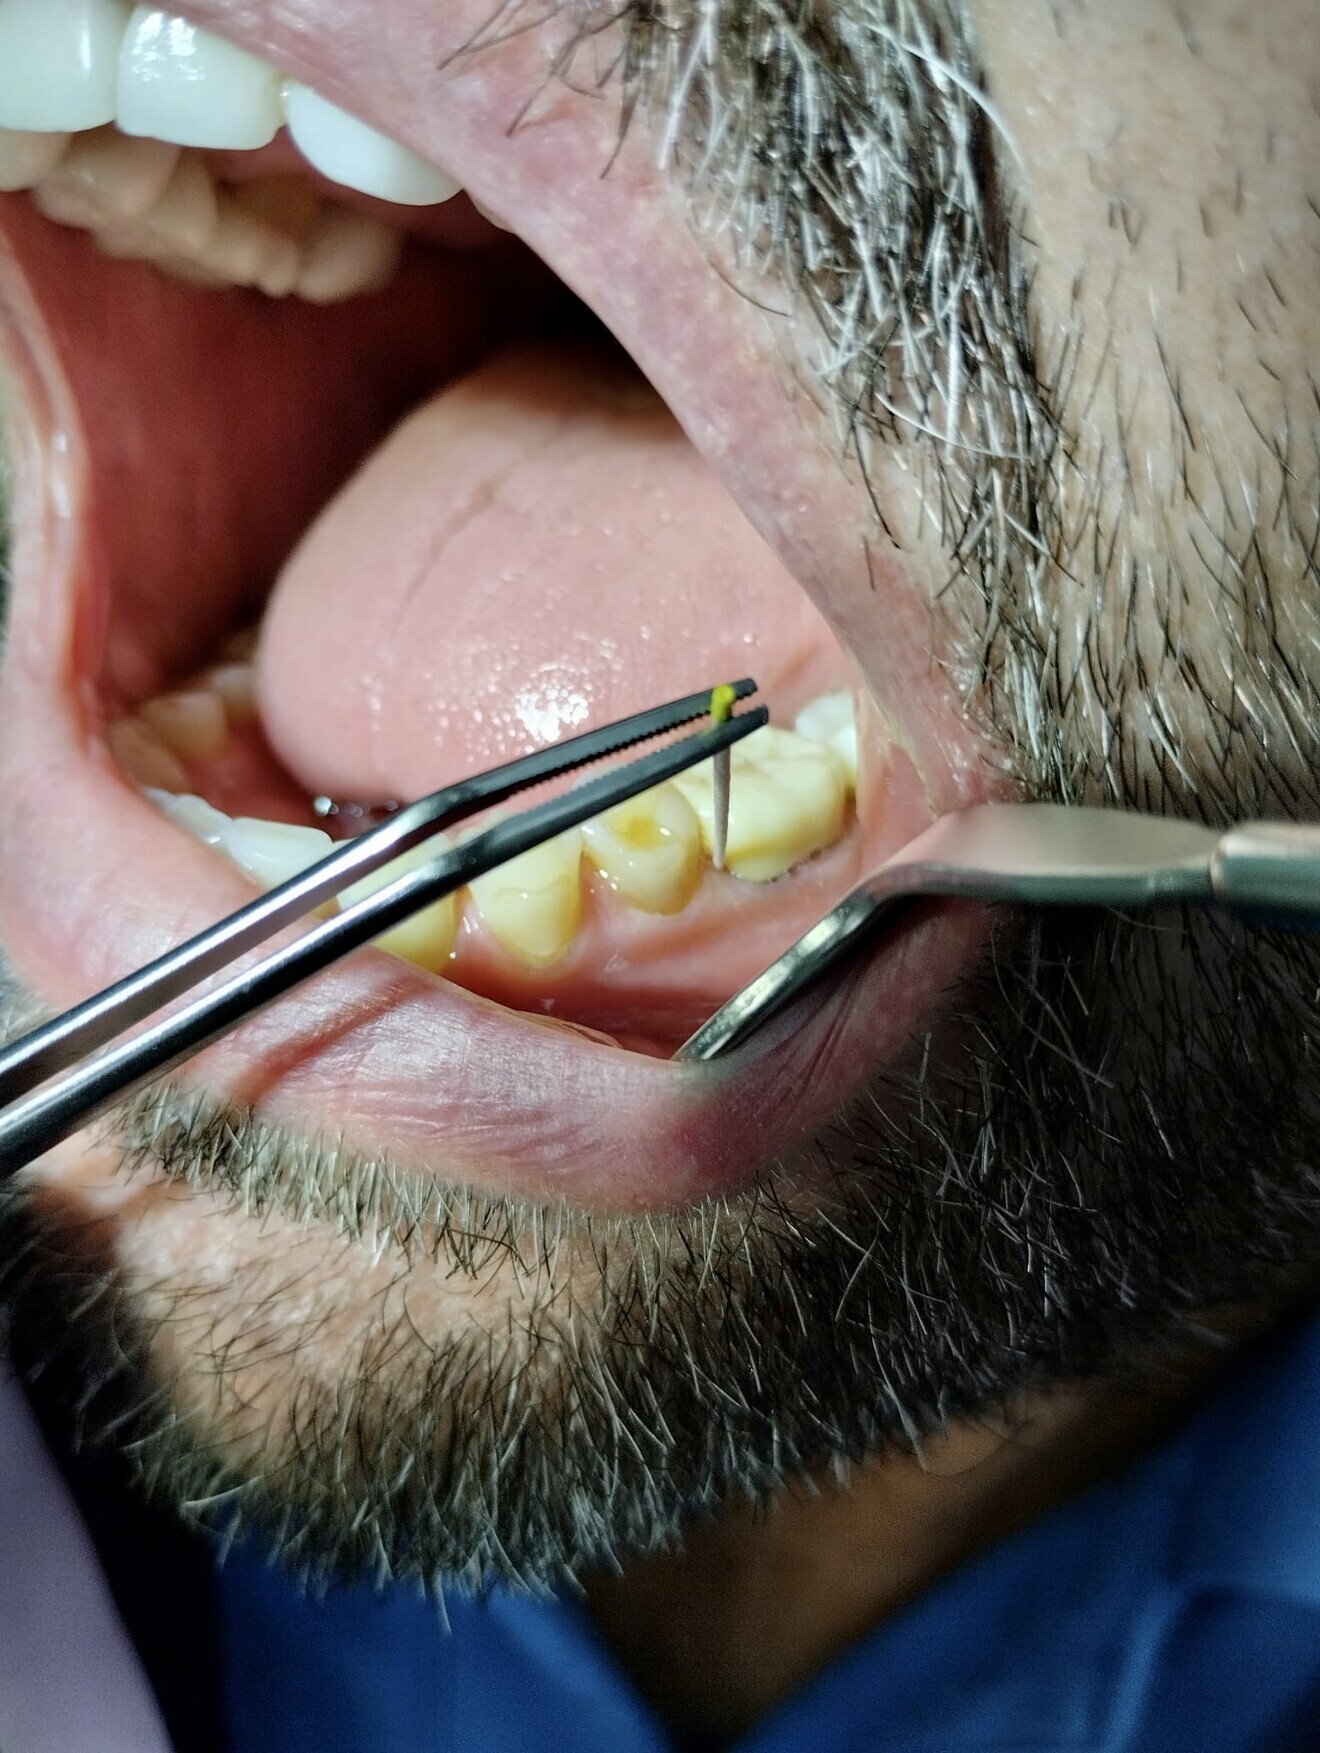

Fig. 2: Measurement before treatment.

Owing to the elevated periodontal screening index values, another appointment was scheduled to assess periodontal status. Both periodontal pocket probing depth (PPD) and bleeding on probing (BOP) and mobility measurement were performed on all teeth (Fig. 2). Tooth #37 had a mobility of Grade I and no probable bifurcations, and teeth #36 and 47 had radiographically visible bifurcations. Given the periodontal status findings, which included PPDs of up to 12 mm (tooth #13) and several PPDs of 7 and 8 mm, along with purulent exudate from the periodontal pockets of teeth #13, 27, 36, 33 and 43, an additional microbiological investigation was initiated (Fig. 3). The analysis results showed an elevated concentration of bacteria such as Tannerella forsythia, Treponema denticola and Prevotella intermedia and a very high concentration of Porphyromonas gingivalis and Aggregatibacter actinomycetemcomitans (Fig. 4).